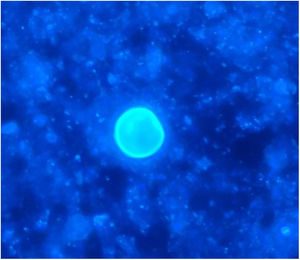

The chest-CT scan showed an extensive right lung consolidation and bilateral nodular consolidative foci (Fig. 1). Empiric liposomal amphotericin B was added to improve fungal coverage. A bronchoalveolar lavage (BAL) was performed. Multiplex PCR for respiratory viruses and bacteria (influenza, respiratory syncytial virus, CMV, adenovirus, coronavirus, rhinovirus, Legionella, Mycoplasma, Chlamydia, Escherichia coli, Klebsiella, Moraxella, Serratia, S. aureus, S. pneumoniae) were negative. No acid-fast bacilli were observed in the auramine stain. On direct examination with Gram and Calcofluor stain of the BAL a microorganism compatible with C. posadasii was found, and later confirmed on cultures (Figs. 2 and 3). The patient continued to require high oxygen requirements and eventually developed multiorgan failure. Nine days after admission the patient died. On the necropsy, spherules full of endospores were found within the pulmonary parenchyma, confirming an invasive fungal infection (Fig. 4).